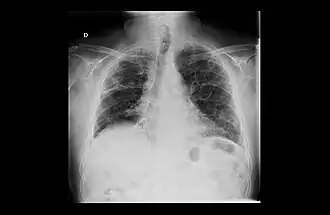

Revmatoidní artritida (RA), odborně arthritis rheumatica, je systémové zánětlivé autoimunitní onemocnění, které vede k chronickému zánětu synoviální tkáně, což má za následek nevratné poškození chrupavek a kostí kloubů.[1][2] RA ovšem nepostihuje jen klouby, ale může vést i k závažným extraartikulárním projevům, kdy zánět může zasáhnout i oči, srdce a plíce a vést ke kardiovaskulárním a respiračním onemocněním.[3][4]

- oční příznaky (záněty skléry)